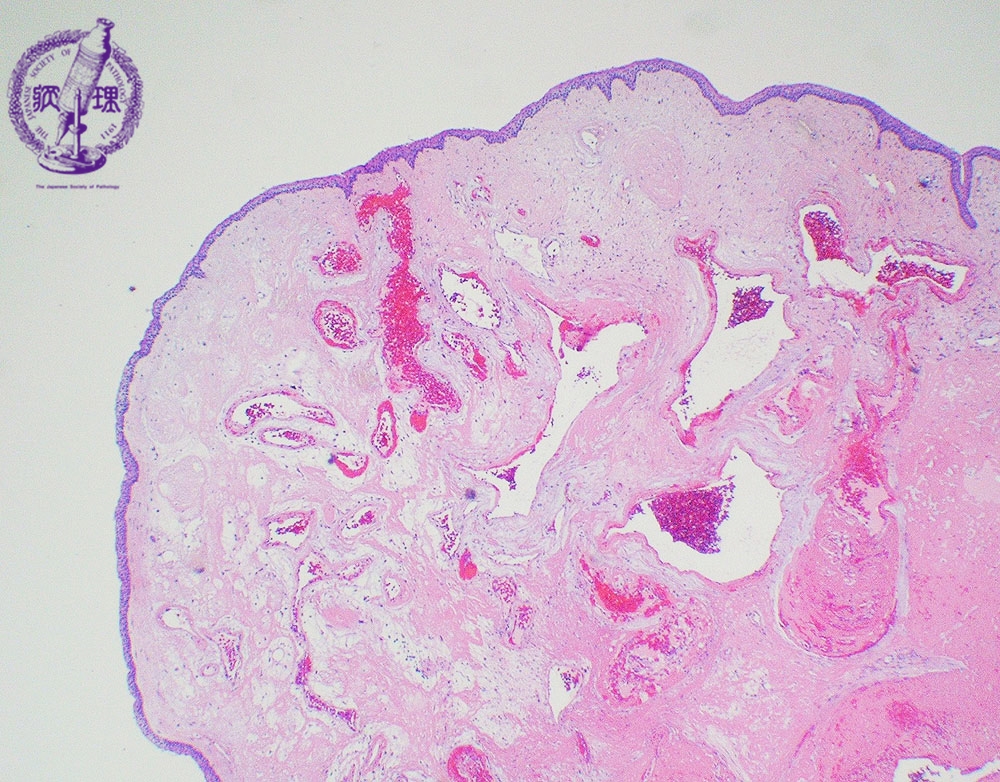

- (3)Laryngeal polyp (nodule)

Microscopic view (low power view): The course, nodular and proliferating fibrotic stroma contains many dilated capillaries (arrow) and is lined by stratified squamous epithelium.